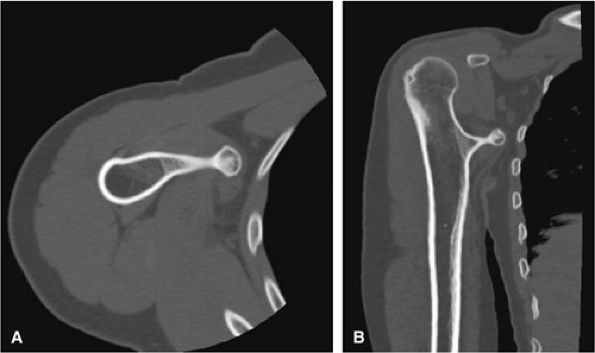

FIGURE 14-27 ● A metaphyseal osteochondroma arising from the proximal humerus with continuity of marrow and cortex is demonstrated on axial (A) and coronal (B) CT images.